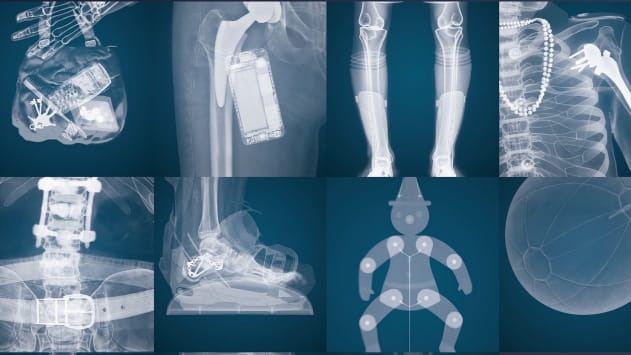

Der Preis würdigte das 2016 lancierte «Knochentram». Es manifestierte die partnerschaftliche Zusammenarbeit mit der Orthopädie Sonnenhof. Gemeinsam gelang uns ein sehr öffentlichkeitsträchtiger Auftritt: Das Tram sollte nicht nur Patienten, sondern die gesamte Öffentlichkeit ansprechen und einen vertieften Einblick in die Welt des menschlichen Bewegungsapparat geben.

Ziel war es, unsere Orthopädie in Bern und Umgebung bekannter zu machen. Im Fokus stand dabei, der breiten Öffentlichkeit in kreativer Weise Wissen über die sieben Spezialgebiete: Hüfte und Becken, obere Extremität, Wirbelsäule, Hand, Fuss und Kinderorthopädie zu vermitteln.

Öffentlichkeitsträchtig: Das «Knochentram» der Berner Verkehrsbetriebe Bernmobil